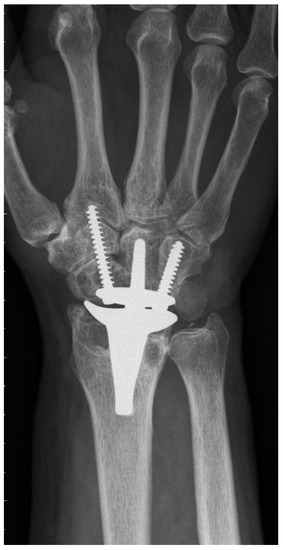

The CRR group showed 17 complications in 15 wrists. The most common one was radial impaction (n = 10) (Figure 2), leading to four re-operations including scaphoidectomy. Moreover, we could detect two ganglions, one complex regional pain syndrome, and one postoperative surgical site infection, which could successfully be treated with antibiotics. One patient received De Quervain’s tenosynovitis release. One patient presented with continuous pain in the region of the hamate with simultaneous radiolucency around the ulnar screw. During revision surgery, the loose ulnar screw was exchanged to a longer one. Another patient developed massive pain due to radial screw breakage, which was treated by exchanging the broken screw. Radiological abnormalities were observed in 19 patients: radial radiolucency (n = 19), carpal radiolucency (n = 14), and screw breakage (n = 1).

To the best of our knowledge, PRC has never been previously described for primary TWA implantation in the current literature (see Table 5 for a summary of the literature). Gupta merely described, in his original surgical technique for ReMotion prosthesis, a salvage procedure for failed PRC or failed 4-corner fusions using TWA [1]. Interestingly, he recommended harvesting the pisiform for reconstruction of the missing distal pole of the scaphoid, where the radial screw is consecutively inserted. The present study shows that this additional step is not necessary, because fixation of the radial screw in the trapezoid and second metacarpal is sufficient for applying slight compression and rotational stability to the carpal prosthesis. Conney et al. [9] are the only authors who reported details on their carpal resection technique (i.e., the manufacturer’s recommended technique). Interestingly, we also found in the manufacturer’s operative technique that the producer recommends a more distal resection in patients with excessive carpal erosion or advanced degenerative joint disease [10]. However, we assume that this adaption would probably also not prevent TWA patients from being prone to suffering from radial impaction syndrome. This predominant clinical complication in the CCR group is most probably caused by the remaining distal pole of the scaphoid. Radiographically, this issue can be perfectly illustrated: Figure 2 shows a dorsopalmar radiograph of the wrist in neutral position with respect to radial and ulnar deviation (the third metacarpal and the long axis of the metacarpal are perfectly aligned). Even in this neutral position—without actively radially deviating the carpus—one can see contact or impingement between the prosthesis’s radial socket and the distal pole of the scaphoid. This situation led to four reoperations including resection of the distal pole of the scaphoid, which completely resolved the patient’s complaints. This further confirms the hypothesis of a correlation between the CCR technique and radial impaction syndrome. Moreover, we suppose that this complication is due to particular challenges associated with TWA. Inspecting the postoperative radiograph in Figure 1a, due to a sufficient distance between the socket and the scaphoid, the before-mentioned issue of radial impaction syndrome would be difficult to comprehend or predict. Despite intraoperative visual and fluoroscopic evaluation for any impingement in every extreme position while performing the CCR technique, radial impaction syndrome seems to develop in the postoperative course. One of the main reasons might be that TWA is very prone to periprosthetic, osseous remodeling. Osteophytes and osteolysis might cause or aggravate the morphologic correlate of radial impaction syndrome, which can be seen in Figure 2. This 6-year postoperative radiograph was taken from the same patient as in Figure 1a. The phenomenon has already been observed by Boeckstyns and Herzberg [11], who discuss possible reasons for osseous reactions in TWA. This publication mainly focused on radiolucency, which also represented a clinically asymptomatic, radiographic abnormality in both our cohorts.

Figure 2. Final radiograph (72 months postoperatively) of a CCR cohort patient with massive radial impaction syndrome.